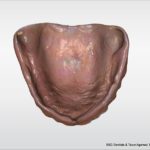

A patient with existing dentures comes back to our office for new dentures. She has an upper complete and a 2 implant lower overdenture. In this past this would necessitate either duplicating the existing dentures (a complete pain), starting from new tissue level impressions, or using existing as trays and having lab return them same day and have the patient go without her teeth (both of which are hard to coordinate).

Instead we are able to take a double sided digital impression of the upper and lower denture while in occlusion. This begins the transfer and communication to the laboratory.